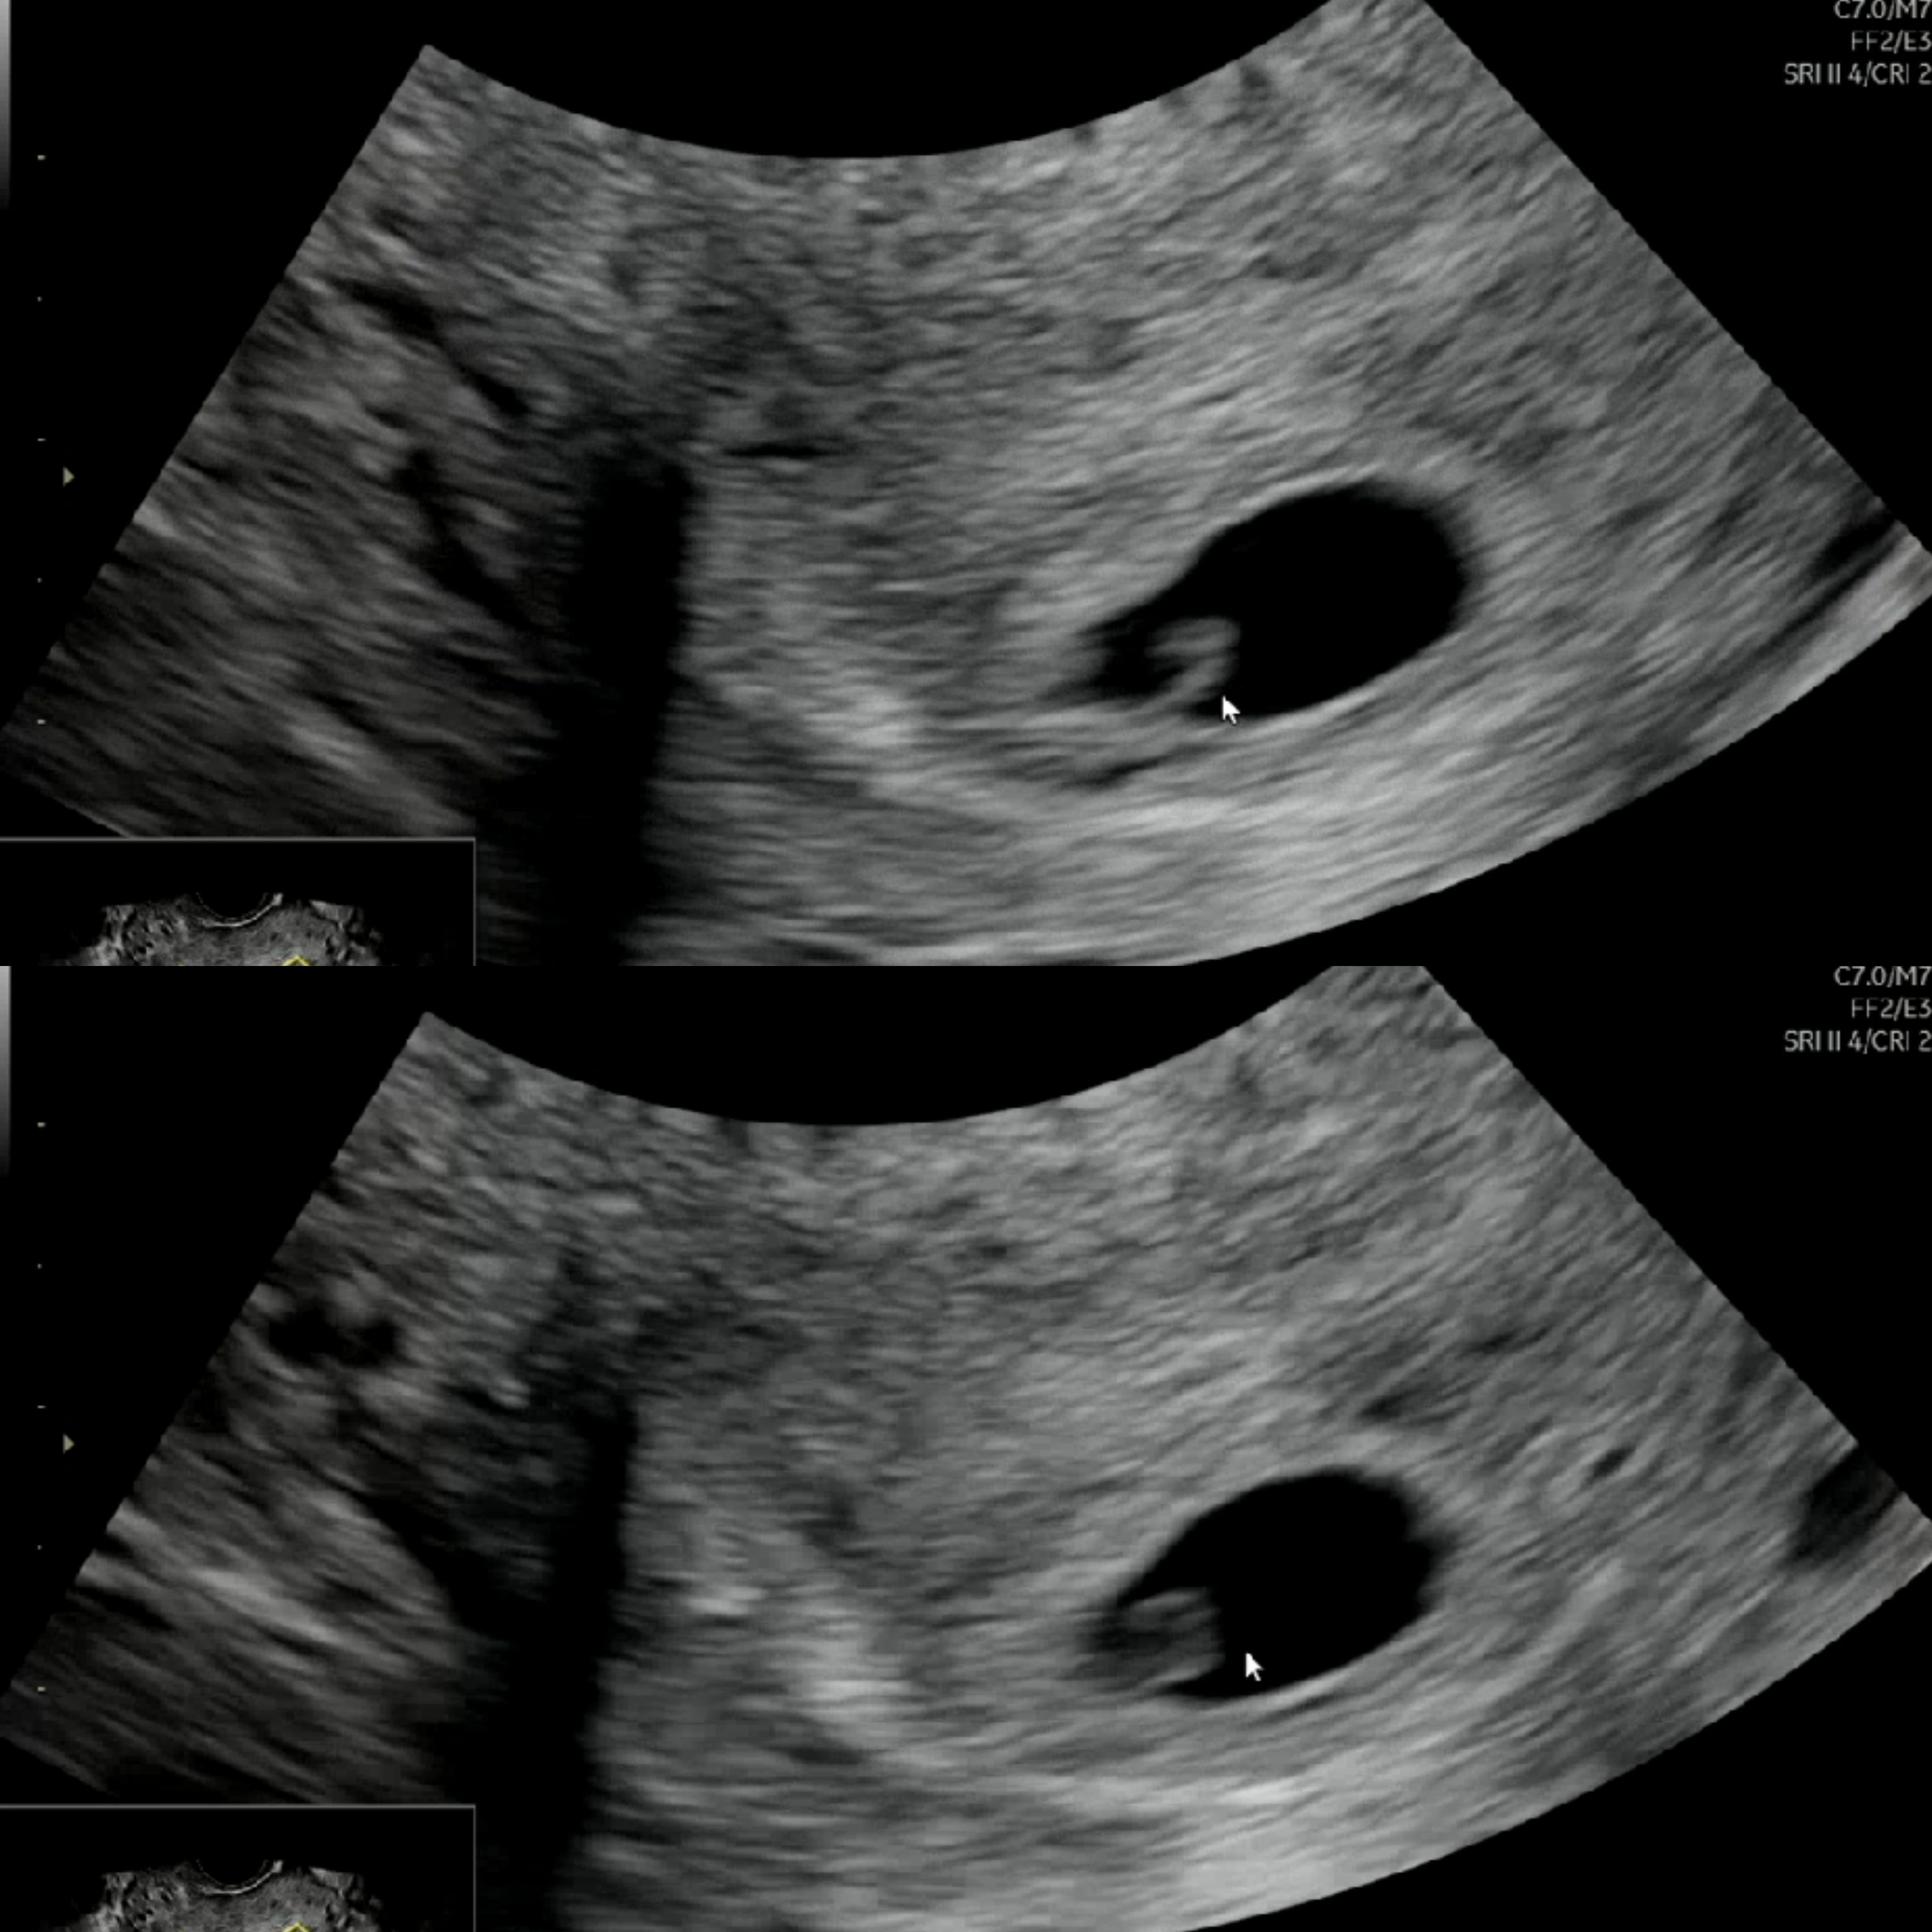

11월24일 월요일 아기집 0.44 확인 오늘 11월29일 토요일 아기집 1.33 확인 난황확인 6주1일이라고 되어있어요 제가보기엔 난황으로만안보이고 태아로도보이는거같은데 아닌가요? 심소는 체크도 안해주셨어요그냥 난황이라고하셨어요 이렇게커요 난황?

난황이 이렇게 구불? 큰지 몰랐어요!ㅠㅠ 심소듣기 너무 힘드네용..ㅠㅠ